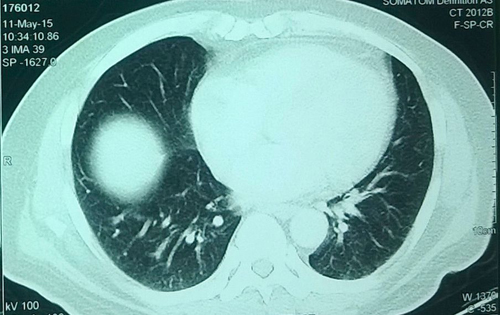

Kết quả chụp X-quang khối u thận của ông Kapleshwar Lal Das. Ảnh: Barcroft

Ông Kapleshwar Lal Das, sống ở New Delhi, phải đến khám ở Viện Khoa học Y khoa Ấn Độ do thấy khó chịu trong người và ho nhiều.

Sau khi kiểm tra, các bác sĩ phát hiện ra một khối u nặng 5,018 kg, tương đương kích cỡ một quả dưa hấu lớn, trong thận của bệnh nhân này. Ông Kapleshwar lập tức được đưa vào phòng phẫu thuật để cắt bỏ khối u khổng lồ.

Ca mổ kéo dài 5 giờ và các bác sĩ khẳng định đây chắc chắn là khối u thận lớn nhất thế giới từ trước tới nay.

Tiến sĩ Mukur Dipi Ray, người chịu trách nhiệm chính của ca phẫu thuật, cho biết: "Chúng tôi đã tiến hành mổ phanh bụng bệnh nhân để cắt bỏ khối u khổng lồ ra khỏi cơ thể. Nó nặng gấp nhiều lần một khối u thông thường, bám chặt vào gan và đại tràng".